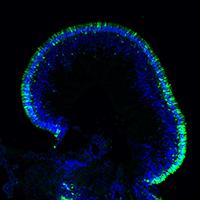

A complementary approach to understanding genes important in optic fissure closure in humans is the laboratory use of animal models. We use mouse and zebrafish models to better understand how genes are regulated during the course of optic fissure closure. Specific mutant mouse strains are also being investigated to discover genes that might cause coloboma in humans. These studies have identified that two zinc finger proteins, Nlz1 and Nlz2, regulate optic fissure closure, perhaps through a Pax2-dependent mechanism. We are currently trying to understand the developmental role of these and other genes from our screen in the normal process of optic fissure closure and to search for causative mutations in humans.